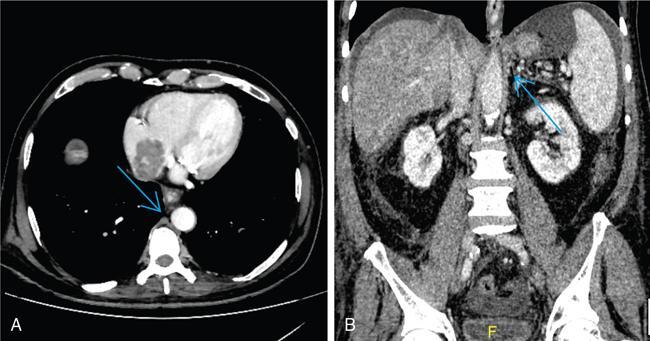

Shrinivas B. Desai, Ritu K. Kashikar, Aman Snehil, Ajay Jhaveri Cirrhosis is a late stage of irreversible scarring of the liver causing abnormality in liver structure and function. Multiple conditions and factors can cause repeated liver damage and scarring ultimately leading to cirrhosis. The most feared complication of liver cirrhosis is the development of hepatocellular carcinoma (HCC). Portal hypertension (PHT) is seen with a variety of conditions but cirrhosis happens to the most important cause. Imaging plays a vital role in noninvasive diagnosis and treatment planning of both cirrhosis and PHT. Liver imaging reporting and data system (LI-RADS) is a standardized reporting system assigning an observation risk of representing HCC. This chapter focuses on discussing aetiologies and imaging of PHT with a lucid review of L1-RADS 2018 version. The portal blood circulation is a unique circulatory circuit as it connects two capillary beds between the liver parenchyma at one end and the gastrointestinal tract and splenic parenchyma at the other end. The portal system ramifies in the liver and ultimately ends in the hepatic sinusoids from where the blood ultimately drains into the inferior vena cava (IVC). The portal vein (PV) originates from the capillary beds in the stomach, intestine and the spleen. The main PV is formed behind the neck of the pancreas by the confluence of the superior mesenteric vein (SMV) and splenic vein. It continues to the porta hepatis where it bifurcates into the left and right branches as it carries nutrient rich but oxygen poor blood to the liver (Fig. 9.9.1). The PV makes up for 75%–80% of the liver’s blood supply while the hepatic artery which arises from the celiac trunk makes up for the remaining 25%. A pathological increase in the portal venous pressure is referred to as PHT. PHT is most often a sequel of chronic parenchymal liver disease and leads to major life-threatening complications due to bleeding from the collateral circulation (most commonly oesophageal varices). Direct measurement of portal pressure (PP) is invasive and often not feasible in most patients and thus imaging plays an important role in the diagnosis of PHT and its complications. The normal portal venous pressure ranges between 5 and 10 mmHg, which is the equivalent of 7–14 cm H2O. The normal hepatic venous pressure gradient (HVPG) is the pressure gradient between the PV and the IVC, is typically 1–5 mmHg. Presence of PHT is indicated by a wedged hepatic venous pressure of more than 5 mmHg. Other definitions include a splenic pressure of more than 15 mmHg or an intraoperative PP of greater than 30 cm H2O. The complications of PHT are seen when HVPG is greater than 10 mmHg and hence this value defines clinically significant PHT. Variceal bleeding is seen with a pressure greater than 12 mmHg. In ideal conditions, the portal circuit is a high flow, low resistance circuit as it has to allow substantial flow rates of 700–1000 mL/min to the hepatic parenchyma from the gastrointestinal tract. Anatomical changes in the organization of the hepatic lobule can result in rise in the portal resistance. These can occur in the form of collagen deposition in the space of Disse, fibrotic scars formed due to regenerative nodule (RN) formation, loss of normal elasticity of the endothelium and distal venous thrombosis. Changes in splanchnic haemodynamics due to factors that increase splanchnic blood flow and increase in intrahepatic vascular resistance due to transformation of stellate cells into myofibroblasts also contribute to the increase in PP gradient. In Western countries, alcoholic cirrhosis and viral cirrhosis are the leading causes of PHT and oesophageal varices. The viral causes form majority of cases leading to cirrhosis and PHT in the Far East and Middle Eastern countries while Schistosomiasis remains an important cause in the African countries. Worldwide, nonalcoholic steatohepatitis (NASH) and hepatitis C are the emerging causes of chronic liver disease (CLD) and PHT. PHT can be classified as cirrhotic and noncirrhotic depending on whether it is associated with cirrhosis or not. This distinction is important as noncirrhotic causes like PV thrombosis are at high risk of development of bleeding but tend to have a better chance of surviving a variceal bleed than a patient with decompensated alcoholic cirrhosis due to preserved hepatic synthetic functions in the former. PHT can also be classified on the basis of the location of the pathology into prehepatic, hepatic and posthepatic causes. Hepatic causes can further be divided into presinusoidal, sinusoidal and postsinusoidal. The causes of portal hypertension have been denoted in Table 9.9.1. The direct measurement of the PP by measuring the HVPG is invasive, expensive not readily available in all patients. Thus, imaging plays an important role in the diagnosis of PHT. Various modalities are used for the imaging diagnosis of PHT. Ultrasonography (USG) and Doppler evaluation have the advantage of being inexpensive, readily available and bedside modality (Table 9.9.2). The role of ultrasound and Doppler in imaging of PHT is to: Grey scale imaging is useful in evaluating the splenoportal anatomy. The evaluation should begin with the liver morphology. Signs of cirrhosis like nodularity of the liver surface with relative atrophy of the right lobe and prominence of the left lobe and caudate should be looked for. Hepatic echotexture appears coarse and more echogenic (Table 9.9.3). Increase in portal venous diameter is a sign of PHT (Fig. 9.9.2). Portal venous diameter of more than 13 or 15 mm has low sensitivity for diagnosing PHT of only 40%–12.5%, respectively. Absolute measurement of the portal diameter as a sign of PHT is also fallacious as in presence of collateral circulation or hepatofugal flow; there may actually be a decrease in the PV diameter. Therefore, a more accurate sign is respiratory variation of PV diameter. An increase in PV diameter of less than 20% with deep inspiration has been reported to indicate PHT with a sensitivity of 80% and specificity of 100%. This has been reported to be an accurate indicator of cirrhosis. Hepatic vein straightness, uniformity of vein wall echogenicity and visualization of at least 1 cm segment of the hepatic vein are the parameters used for evaluation. Splenomegaly is defined as bipolar splenic diameter of greater than 12 cm or largest splenic cross-sectional area passing through the hilum of greater than 45 cm2, and occurs secondary to PHT (Fig. 9.9.3). A total of 65%–80% patients with cirrhosis have splenomegaly on ultrasound. Patients with cirrhosis due to viral hepatitis and primary biliary cirrhosis show splenomegaly more frequently than those with alcoholic cirrhosis. This is an accurate sign of PHT. USG is extremely sensitive with respect to detecting subclinical ascites. Perihepatic space is the most usual site of visualization of minimal ascites. In normal subjects, this ratio is approximately 0.07 and a value above 0.1 suggests the diagnosis of PHT with a 95% sensitivity and specificity. The normal spectral waveform of the hepatic artery is a low resistance flow pattern with forward flow in diastole and a resistivity index in the range of 0.5–0.7. In PHT, the resistivity index of the hepatic artery increases with high resistance flow pattern due to increased peripheral vascular resistance. Resistance index (RI) > 0.78 in the intrahepatic branches of the hepatic artery has been reported to have a sensitivity of 50% and a specificity of 100% for the detection of PHT (Fig. 9.9.11). Pulsatility index (PI) > 1.05 suggests severe PHT with a sensitivity of 86% and specificity of 88% (Fig. 9.9.11). Patency of hepatic veins should be evaluated to rule out Budd–Chiari syndrome as a cause of PHT. The normal hepatic venous waveform (HVW) reflects right atrial activity and this results in a triphasic waveform with one positive and two negative waves. In PHT, this waveform becomes monophasic or biphasic. A monophasic HVW has a sensitivity and specificity of 74% and 95%, respectively, in the diagnosis of severe PHT (Fig. 9.9.12). Dilatation of the splanchnic veins – the SMV and the splenic vein – more than 11 mm are suggestive of PHT with a sensitivity and specificity of 72% and 100%, respectively. A reduction in the respiratory variation of the splenic vein and SMV to less than 40% had a sensitivity and specificity of 79.7% and 100%, respectively, for the diagnosis of PHT (Fig. 9.9.13). The splenic artery reveals an increase in the resistivity index and an RI of >0.63 and a PI of >1 have a sensitivity and specificity of 84.6% and 70.4% for the diagnosis of PHT. Presence of portosystemic collaterals like patent paraumbilical vein, dilated left gastric and short gastric veins are 100% specific sign for PHT (Figs. 9.9.14–9.9.16). Recanalization of the paraumbilical vein, known as the Cruveilhier–Baumgarten syndrome is observed in 43% of patients with PHT, and this is the easiest collateral to assess during the US examination. Various portosystemic collaterals that occur in PHT have been discussed in details in subsection on CT findings in PHT. No Doppler parameter is considered reliable enough to measure PP with sufficient accuracy for use in clinical practice. Oesophageal varices are often present in patients with portosystemic collaterals. Appearance or increase in number of collaterals along with splenomegaly has a high association with variceal formation and growth. USG helps in diagnosis of prehepatic causes like portal stenosis or thrombosis by demonstrating the patency and morphology of the splenoportal system. Arteriovenous fistulae and tumours causing vascular thrombosis as aetiology can be readily detected. USG helps in diagnosis of features of cirrhosis and thus helps differentiate noncirrhotic causes of PHT. USG allows diagnosis of fatty liver disease, which is an emerging cause of cirrhosis. Among the posthepatic causes, USG aids in establishing the diagnosis of Budd–Chiari syndrome by demonstrating the patency and morphology of the IVC and hepatic veins. Owing to the inability of CT to detect flow direction, portal flow rates or pressure gradients, CT is not the primary modality in diagnosis of PHT. Similar to USG dilatation of portosystemic system is a feature of PHT (Fig. 9.9.17). Changes in cirrhosis if present can be seen in the form of surface nodularity, nodules and fibrous septae. CT plays an important role in diagnosis of portal venous thrombosis and evaluating its extent. An acute thrombus is seen as a hypodense filling defect in the vessel causing distension of the venous lumen. Surrounding fat stranding can be seen. A chronic thrombus appears as an eccentric filling defect usually along the wall and is often associated with decrease in vessel diameter. Calcification may be seen in chronic thrombi. Multidetector computed tomography (MDCT) is a useful tool to evaluate portosystemic collateral circulation and recognize complications of PHT. 3D angiography can help understand portal venous and complex variceal anatomy and plan treatment. The various portosystemic collaterals are discussed below. They can be classified into those draining into superior vena cava (SVC) and those draining into the IVC. Magnetic resonance imaging (MRI) is a noninvasive modality used in the evaluation of PHT without the use of ionising radiation. It provides evaluation of parenchymal abnormalities, collaterals and characterization of tumours (Fig. 9.9.28). Spin echo sequences allow characterization of liver masses and liver parenchyma. Loss of flow void allows for detection of thrombosis. Time-of-flight (TOF) angiography is useful in assessing the portal venous system and allows for successful detection of PV thrombosis. The disadvantages of TOF are motion artefacts caused by breathing, long acquisition times and incomplete coverage of the portal venous system. Novel imaging techniques include phase contrast, T1 mapping and magnetic resonance elastography (MRE). The advantage of phase contrast over TOF imaging is that phase contrast imaging acquires information regarding the flow direction in addition to the information regarding the flow velocity. On-phase contrast images signal within vessel is hyperintense when flow is cranial and hypointense when flow is caudal. Look-Locker imaging technique using gradient echo (GRE) MRI sequences with inversion recovery pulse is used to quantify fibrosis by measuring precontrast T1 relaxation times. Interventions in PHT can be aimed at diagnosis or more commonly at management of complications of PHT. HVPG measurement, which is the gold standard for the diagnosis of PHT, can be achieved through cannulation of the PV. Transjugular hepatic biopsy is another diagnostic invasive technique that also allows indirect measurement of PP. Disadvantages include deterioration of hepatic function caused by diversion of portal venous blood flow and shunt dysfunction. TIPSS is contraindicated in patients with congestive heart failure, severe pulmonary hypertension, severe tricuspid regurgitation and hepatic failure. In this technique, a catheter is advanced from the femoral vein into the outlet of the gastrorenal, usually in the region of the left renal vein. The shunt is then occluded with a balloon and sclerosant is injected retrograde to occlude the gastric varices. Histological development of RNs surrounded by fibrous septae in response to chronic liver injury, progressing PHT and end-stage liver disease is termed as cirrhosis. Although initially considered an end-stage phenomenon in CLD, recent evidence suggests that the histological fibrosis can be reversible in early stages with the initiation of specific therapies, for example, in viral cirrhosis with the initiation of antiviral therapy. The one-year mortality rate in cirrhosis varies widely from 1% to 57% depending on the occurrence of complications. Cirrhosis can have a wide variety of causes ranging from congenital to acquired and infectious to noninfectious. It is also a major aetiologic risk factor for the development of HCC. Imaging plays an important role in aetiologic diagnosis of this diverse entity as well as in the diagnosis and management of its complication and surveillance for oncological transformation.